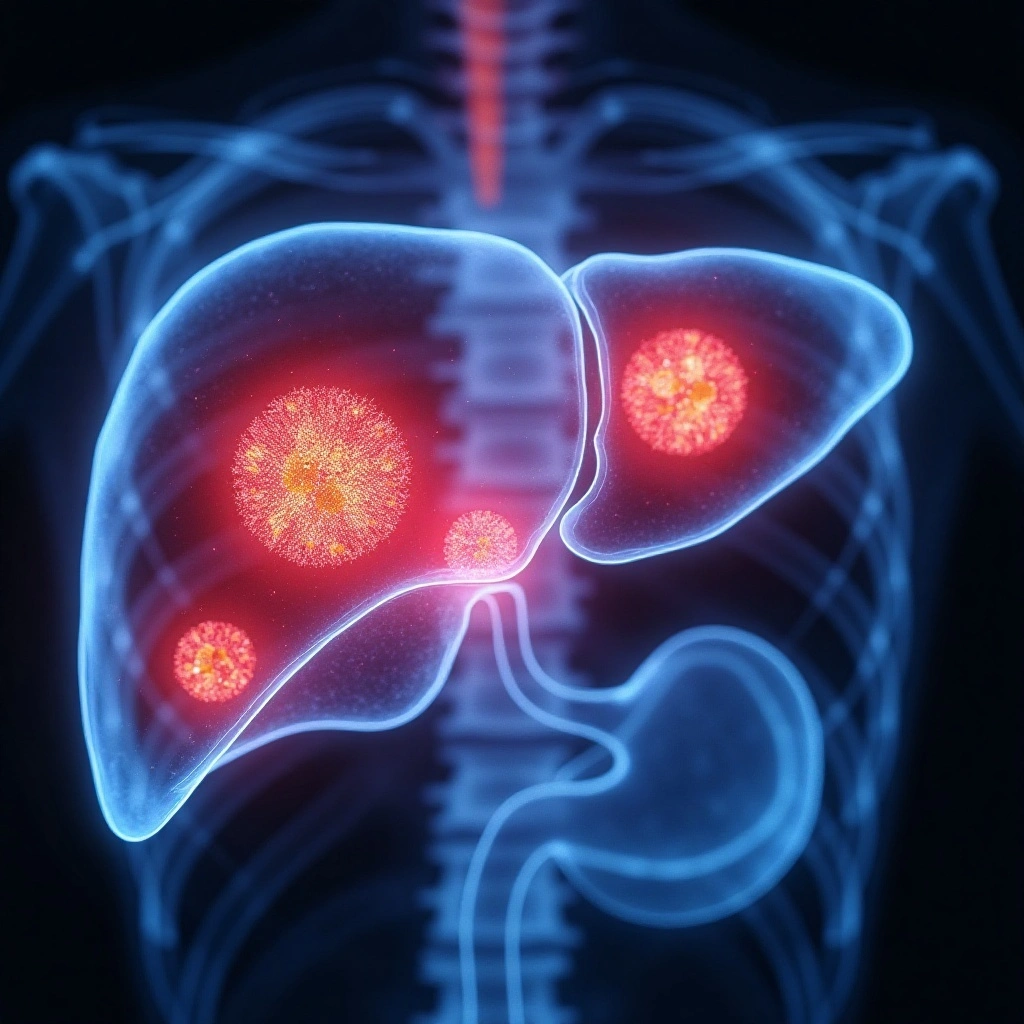

Consult a leading hepatologist in Ahmedabad at drmanasvaishnav.com for liver, pancreatic, and gastrointestinal disorders, including liver biopsy, transplant support, endoscopic procedures, and personalized treatment at Shalby Hospitals and regional clinics.